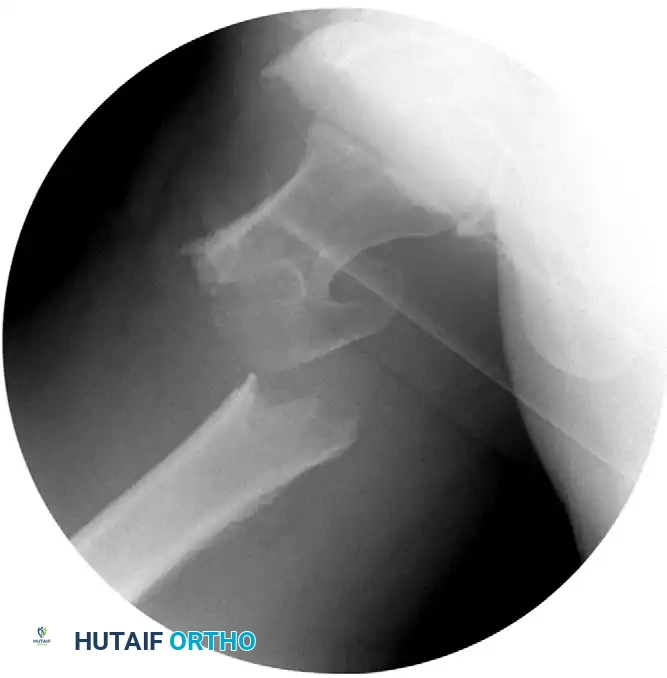

CLOSED REDUCTION MANEUVERS

Surgical Warning: Never proceed with the surgical incision until an acceptable closed reduction is confirmed on both AP and lateral fluoroscopic views. A poorly reduced fracture cannot be salvaged by a perfectly placed implant.

- Standard Reduction: Reduction of the affected extremity is typically achieved through longitudinal traction followed by internal rotation. The internal rotation corrects the external rotation deformity caused by the short external rotators and gravity, bringing the femoral neck parallel to the floor.

- Correcting Sagittal Deformity: The most common sagittal plane deformity is a posterior sag of the fracture site. This may require correction via an anteriorly applied force (e.g., a crutch or a specialized reduction tool placed under the posterior thigh) to lift the distal fragment before finalizing the reduction with traction and internal rotation.

- Fluoroscopic Scrutiny: Carefully scrutinize the images to rule out varus deformity, posterior sag, and excessive internal rotation. A slight valgus reduction is biomechanically superior to any degree of varus.